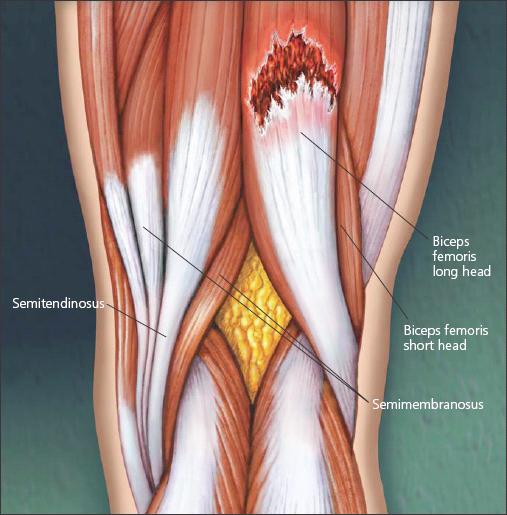

Muscle groups are composed of tendon-muscle-tendon units that span one or more joints. Contractions of muscle groups induce and control joint motions. For example, the hamstring muscles (semimembranosus, semitendinosus, and biceps femoris) run from the pelvis and femur to the back and side of the knee; with their attached bones, they make up contractile units that stabilize the knee and hip and allow their motion (Figure 1). Injury occurs at the weakest part of the unit.

Figure 1 –

The most frequently strained muscle group is the hamstring,which consists of the semimembranosus, semitendinosus, and biceps femoris muscles.The hamstring is more susceptible to strain injury because it crosses more than 1 joint. A muscle tear of the long head of the biceps femoris is illustrated.